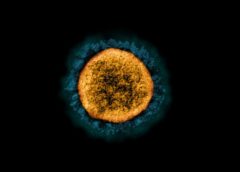

阅读全文世界首例故意感染新冠志愿者的研究取得初步成果

一项对故意感染SARS-CoV-2的健康成年人进行的具有里程碑意义的研究的初步结果揭示了对COVID-19最早阶段的新的和意想不到的见解。这些数据表明,该病毒的潜伏期比预期的要短,…